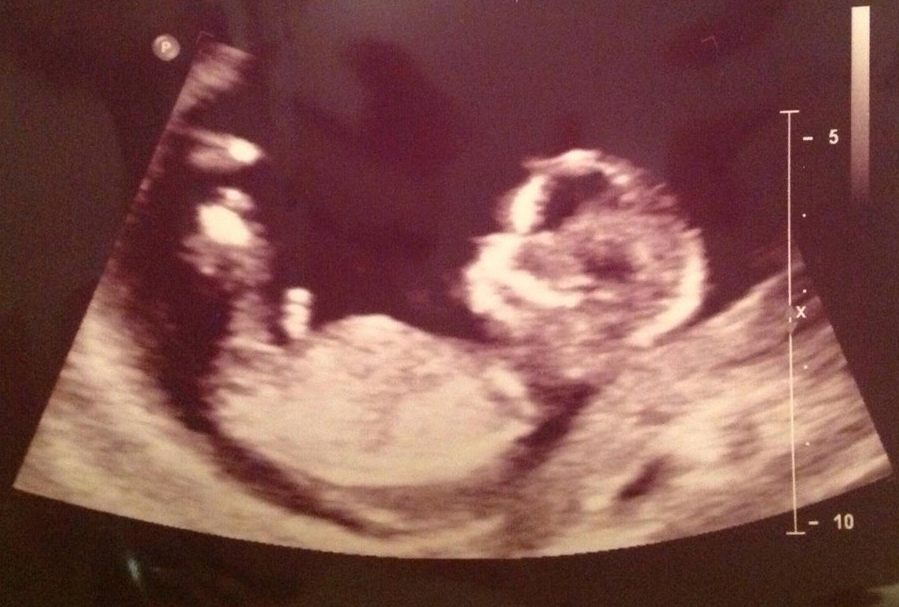

Hi! She is 13 weeks along. What do you think? I think the nub is visible, but maybe I'm wrong! Boy or girl if it's visible?

Very hard to see, but if I had to guess I would probably lean more towards girl....

I'd say girl too

Im leaning girl.

Hmm. Not sure all of the nub is there. But if I had to guess on this alone, I'd lean pink.

girly